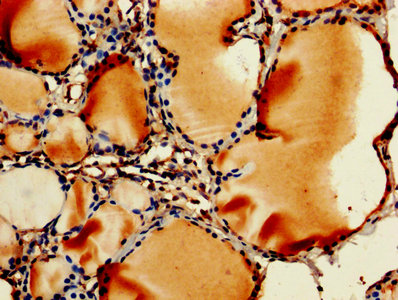

• IHC image of CSB-PA00065A0Rb diluted at 1:250 and staining in paraffin-embedded human thyroid tissue performed on a Leica BondTM system. After dewaxing and hydration, antigen retrieval was mediated by high pressure in a citrate buffer (pH 6.0). Section was blocked with 10% normal goat serum 30min at RT. Then primary antibody (1% BSA) was incubated at 4°C overnight. The primary is detected by a biotinylated secondary antibody and visualized using an HRP conjugated SP system.